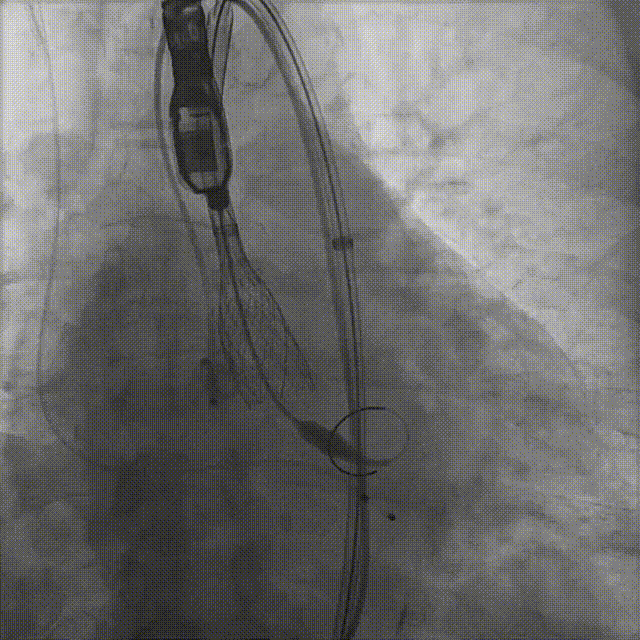

病例概览

患者病史 体检发现心脏瓣膜病半月余,平素无症状 ,有高血压病史。 后来院复查诊断为:主动脉瓣狭窄(重度)、先天性主动脉瓣二叶瓣畸形、心室肥厚、升主动脉扩张心功能 I 级(NYHA 分级)、高血压病 2 级(极高危)。 术前 CT:Type0型二叶瓣,瓣叶增厚,无钙化,类风湿性;瓣环径25.6mm,LVOT稍收窄,瓣环水平夹角66.6°,轻微横位心;左右冠开口高度可,瓣叶不长,无冠脉风险;心室收缩末内径约32mm,室壁增厚;外周入路无明显迂曲,无钙化、双侧内径可、双股中分叉,右侧为主入路能够支持20F大鞘通过。 造影角度及入路:LAO 6° CAU 13° 手术策略 采用右侧股动脉为主入路,左侧为辅助入路,常规穿刺。推荐使用20球囊预扩,预装TAV29瓣膜,初始定位对齐瓣环上0mm开始释放。 手术过程 20号球囊预扩无明显腰征 输送器过弓跨瓣顺滑 80%工作位观察 术后造影,瓣膜释放位置良好,无瓣周漏 术后超声:人工生物瓣释放后形态满意,瓣叶开放、关闭活动良好,无瓣周漏;跨瓣血流速度降至 2.5m/s,平均压力梯度6mmHg,符合手术预期。 Prostyle A®预装干瓣——“刚柔并济”助力临床最优化解决方案: 丝滑过弓能力:Prostyle A®短瓣架设计联合远端超滑亲水涂层,即使没有联合使用snare,都可以柔顺过弓,该例横位心的患者更好的展现了输送系统的柔顺性; 平衡的径向支撑力:该例患者Type0型二叶瓣,术后形态展开良好且无瓣周漏,在横位心等复杂情况下实现稳定锚定。 80%可回收设计:80%工作位观察,起搏时间更短,对患者损伤减少到最小,也利于术中精准调整瓣膜位置,保证术后效果。